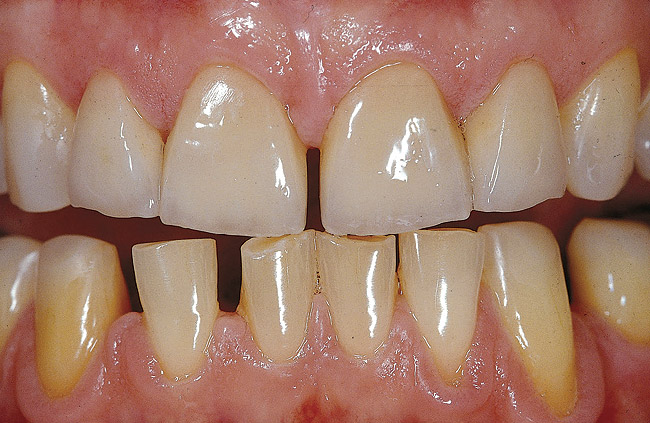

Figure 2a  Immediate dentin sealing is particularly  challenging when dealing with dentin  margins in veneer preparations for anterior  teeth (red rectangle shows the schematic  cross-sectional view of gingival dentin margins  in images C, E, G, I, J, L-N, and P-S).

Figure 2a

Figure 2b  Clinical situation during preparation of the  eroded teeth. Existing restorations, as well  as severe initial erosion and wear, led to the  realization of a shoulder facial preparation.

Figure 2b

Figure 2c  A marked gingival chamfer always facilitates  the application of the dentin bonding  agent. Immediate dentin bonding would not  be possible in the presence of a traditional  light chamfer because the adhesive layer  tends to pull over the margin, creating a feather-  edge finish line and insufficient margin  definition.

Figure 2c

As mentioned earlier, DBA thicknesses can reach several hundred micrometers when applied to concave areas.19 When using IDS, the additional adhesive layer can sometimes negatively affect the thickness of the future restoration. This is particularly evident in the case of porcelain veneers and in the presence of gingival margins in dentin (Figure 2). When margins terminate in dentin, a marked chamfer (0.7 mm to 0.8 mm) is recommended to provide adequate margin definition and enough space for the adhesive and overlaying restoration (Figures 2A through 2C). A shallow chamfer would cause the adhesive resin to pull over the margin and compromise both margin definition and porcelain thickness.9 In other axial locations, confined and superficial dentin exposure gives only a limited space for the restorative materials, including the bonding agent. The application and curing of the DBA would significantly reduce the space left for the ceramic buildup. Considering that a low ratio of ceramic to luting agent thickness can negatively influence the stress distribution within the porcelain,32,33 IDS is not indicated for very superficial dentin exposures. On the other hand, deeper preparation surfaces (ie, in the presence of Class IV or V defects or in the case of inlay/onlay/overlay preparations) can be easily treated with IDS before impression taking because sufficient space is left for the restorative material to maintain a reasonable ratio of thicknesses between the ceramic and the luting agent.

Etching the freshly cut dentin (with H3PO4 for 5 to 15 seconds) must immediately follow tooth preparation (Figures 2D and 2E) to avoid saliva contamination. After rinsing, excess water must be removed. One should be cautious as both excessive drying and excessive wetting can cause an inferior bond owing to demineralized collagen collapse and nanoleakage/water treeing, respectively.36 Accordingly, air drying should be avoided. Excess moisture removal can be achieved by use of suction drying (negative air pressure) (Figures 2F and 2G) without applying positive pressure to demineralized dentin.

The next steps can include the application of either the primer (3-step systems) or the self-priming resin (2-step systems). Practically, the separate primer application should be favored (Figures 2H through 2J), not only because of the superior subsequent bond but also because it allows a more accurate placement of the adhesive resin. In fact, the application of a priming agent or self-priming resin often requires a slight brushing motion, which frequently results in the spread of resin above the exposed dentin limits. There are no consequences when using a separate primer as the latter does not create any detectable thickness or layer. After the suction of the excess solvent (Figure 2J), the adhesive resin can be placed accurately (eg, with a periodontal probe, as in the case of veneer preparation margins [Figures 2K through 2N). On the other hand, the use of self-priming resins generates excesses and may pull over the margin (into the gingival sulcus), requiring additional corrections with a bur, again exposing dentin at the margin.

After a first curing (regular mode 20 seconds [Figure 2O and 2P), a layer of glycerin jelly (air block) is applied to the adhesive and slightly beyond. Additional curing (regular mode 10 seconds) of the DBA through a layer of glycerin jelly is recommended (Figure 2Q) to polymerize the oxygen inhibition layer and prevent interaction of the dentin adhesive with the impression material (especially polyethers). Accurate placement of the adhesive resin is usually confirmed by the removal of the deflection cord as the latter should not adhere to the margin (Figures 2R and 2S).